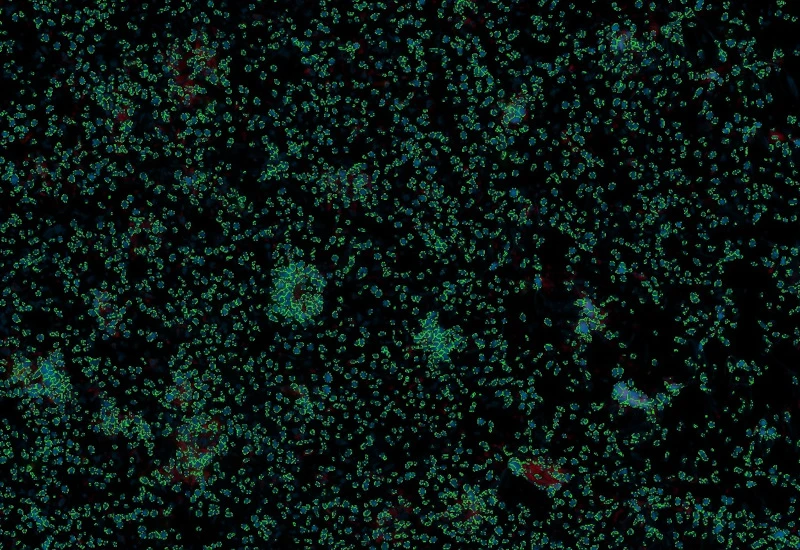

Original image

Nuclei detection